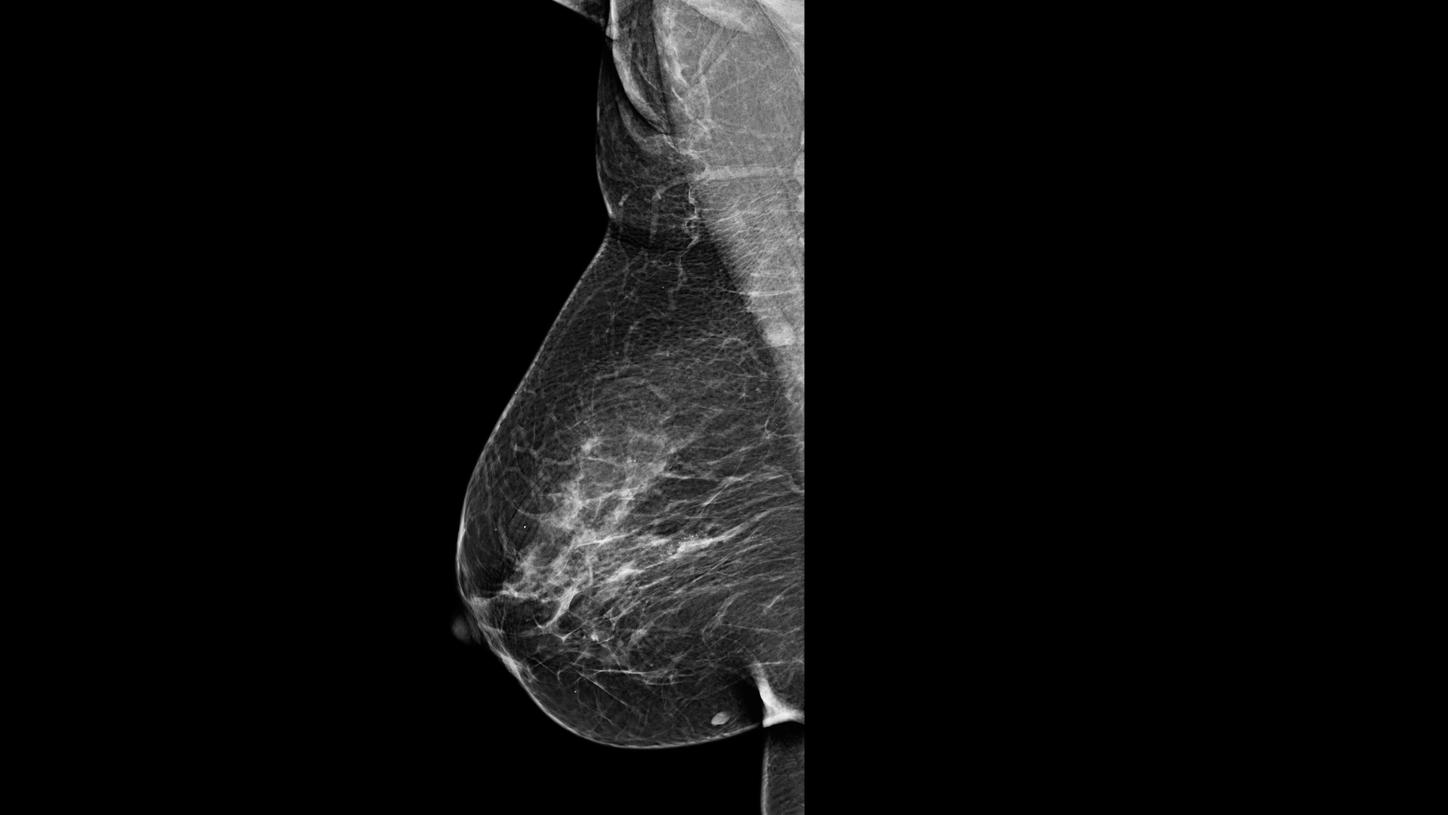

Nesta página, você poderá encontrar periodicamente os casos clínicos mais relevantes, adquiridos com nossas tecnologias em instituições renomadas da América Latina e do mundo. Você poderá revisar os protocolos de aquisição, a evolução final de cada paciente e obter algumas dicas de boas práticas que foram implementadas em cada caso para obter esses resultados.